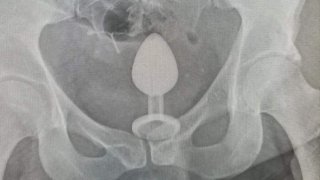

สาวเจ็บรูก้นมาก หลังแฟนสาวพลาดทำของเทียม หลุดเข้าไปในรูก้น

สื่อนอกรายงานว่า "หญิงสาววัย 34 ปี จากเมืองแมนเชสเตอร์ ประเทศอังกฤษ ได้ใช้เซ็กส์ทอยเสียบรูก้น ของแฟนสาวของเธอ แต่ปรากฎว่าพลาดทำเซ็กส์ทอย หลุดเข้าไปในรูก้น เธอลองสาระพัดวิธีการต่างๆ เพื่อเอาออก แต่มันก็เอาออกมาไม่ได้ ในท้ายที่สุดเธอต้องพาแฟนสาวไปโรงพยาบาล เพื่อขอให้หมอเอาออกให้" นายแพทย์ทำการสวมถุงมือยาง ทาสารหล่อลื่นแถวรูก้น เขาค่อยๆสอดนิ้วเข้าไป แฟนสาวเล่าว่า "มันเจ็บปวดเกินจะทนไหว" และ "มันรู้ส.. ดูเพิ่ม